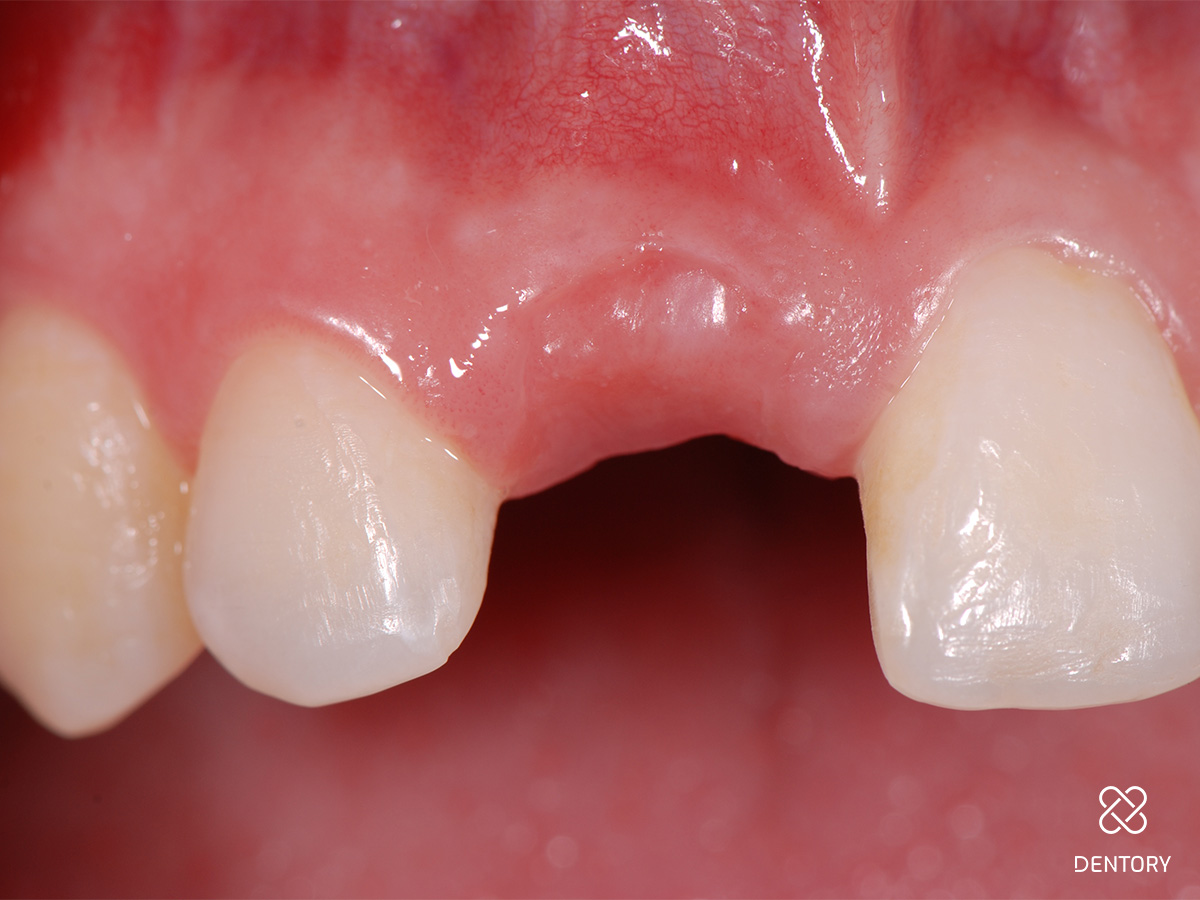

Abbildung 3

...und Entfernung des Zahns durch minimale rotierende Bewegungen mit der Zange.